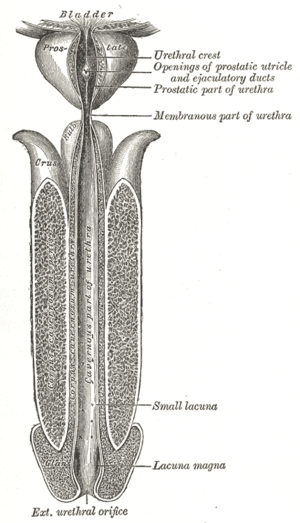

Anatomy of the bladder and outlet

The main organs involved in urination are the urinary bladder and the urethra. The smooth muscle of the bladder, known as the detrusor, is innervated by sympathetic nervous system fibers from the lumbar spinal cord and parasympathetic fibers from the sacral spinal cord.[4] Fibers in the pelvic nerves constitute the main afferent limb of the voiding reflex; the parasympathetic fibers to the bladder that constitute the excitatory efferent limb also travel in these nerves. Part of the urethra is surrounded by the male or female external urethral sphincter, which is innervated by the somatic pudendal nerve originating in the cord, in an area termed Onuf's nucleus.[5]

Smooth muscle bundles pass on either side of the urethra, and these fibers are sometimes called the internal urethral sphincter, although they do not encircle the urethra. Further along the urethra is a sphincter of skeletal muscle, the sphincter of the membranous urethra (external urethral sphincter). The bladder's epithelium is termed transitional epithelium which contains a superficial layer of dome-like cells and multiple layers of stratified cuboidal cells underneath when evacuated. When the bladder is fully distended the superficial cells become squamous (flat) and the stratification of the cuboidal cells is reduced in order to provide lateral stretching.

After urination, the female urethra empties partially by gravity, with assistance from muscles. Urine remaining in the male urethra is expelled by several contractions of the bulbospongiosus muscle, and, by some men, manual squeezing along the length of the penis to expel the rest of the urine.